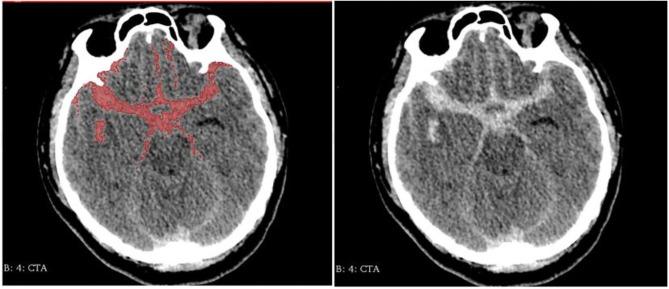

To explore the influencing factors of volume hemorrhage in ruptured anterior circulation aneurysms, so as to identify the characteristics of anterior circulation aneurysms with high volume of hemorrhage, and to provide advice for clinical diagnosis and treatment for those aneurysms. We retrospectively reviewed 437 cases of ruptured anterior intracranial aneurysms in our center between the years 2012 and 2017. According to the inclusion criteria, a total of 100 qualified patients were screened out. We collected demographic characteristics, environmental exposure, and admission status of enrolled patients. In addition, morphological parameters and location of aneurysms were also included. The semiautomatic threshold method was used to measure the volume of hemorrhage. According to the results, the patients were divided into the group with high blood volume and low blood volume. Univariate and multivariate logistic regression analyses were used to discover the related factors affecting the bleeding volume. In univariable analysis, pulse pressure ( = 0.014) showed a significant difference at the < 0.05 test level. In terms of aneurysm morphology, the irregular shape ( < 0.001), calcification ( = 0.001), and flow angle ( = 0.006) showed significant statistical differences between the two groups at the < 0.01 level ( < 0.01). Multivariate logistic regression analysis showed that irregular shape (OR = 5.370 = 0.002 < 0.05), large flow angle (OR = 1.033 = 0.016 < 0.05), and calcification (OR = 5.460 = 0.003 < 0.05) were risk factors for volume of hemorrhage in ruptured anterior circulation aneurysms. The influence of hypertension history was at critical state (OR = 2.877 = 0.051 > 005). According to our analysis results, intracranial anterior circulation aneurysms with irregular shapes, calcifications, and large flow angle are more dangerous. Aneurysms with these characteristics often have a large amount of hemorrhage, requiring timely treatment in clinical practice.

为探讨破裂前循环动脉瘤出血量的影响因素,以明确高出血量前循环动脉瘤的特征,并为这些动脉瘤的临床诊断和治疗提供建议。我们回顾性分析了2012年至2017年间本中心437例破裂的颅内前循环动脉瘤病例。根据纳入标准,共筛选出100例合格患者。我们收集了入选患者的人口统计学特征、环境暴露情况及入院状态。此外,还纳入了动脉瘤的形态学参数和位置。采用半自动阈值法测量出血量。根据结果,将患者分为高出血量组和低出血量组。采用单因素和多因素logistic回归分析来发现影响出血量的相关因素。在单因素分析中,脉压(P = 0.014)在P < 0.05检验水准上显示出显著差异。在动脉瘤形态方面,不规则形状(P < 0.001)、钙化(P = 0.001)和血流角度(P = 0.006)在两组间P < 0.01水平上显示出显著统计学差异(P < 0.01)。多因素logistic回归分析显示,不规则形状(OR = 5.370,P = 0.002,P < 0.05)、大血流角度(OR = 1.033,P = 0.016,P < 0.05)和钙化(OR = 5.460,P = 0.003,P < 0.05)是破裂前循环动脉瘤出血量的危险因素。高血压病史的影响处于临界状态(OR = 2.877,P = 0.051,P > 0.05)。根据我们的分析结果,形状不规则、有钙化且血流角度大的颅内前循环动脉瘤更危险。具有这些特征的动脉瘤往往出血量较大,临床实践中需要及时治疗。